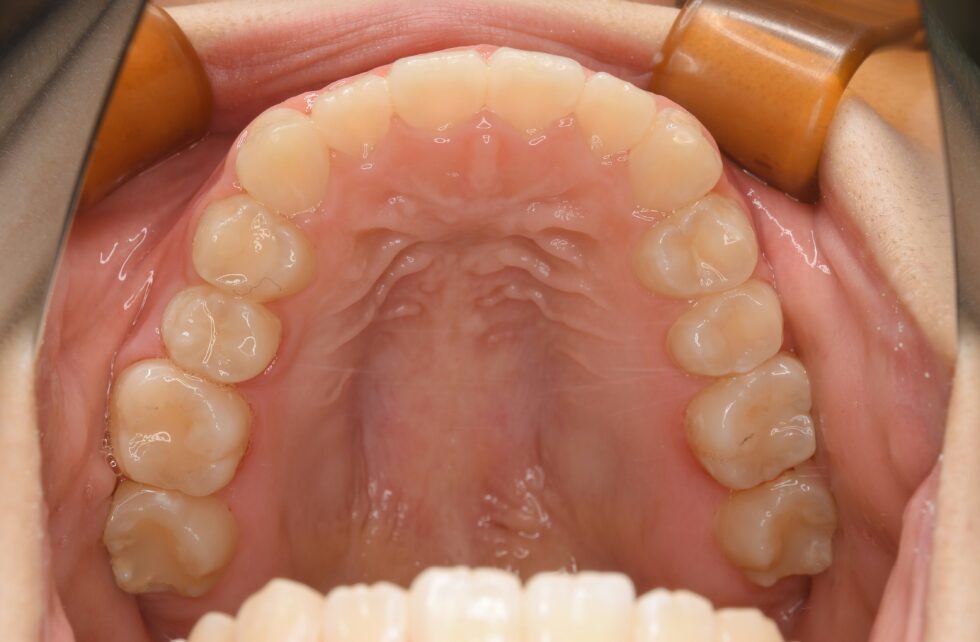

初診時年齢14歳の女子 上顎右側第二小臼歯の埋伏を主訴に遠方の歯科医院より紹介来院した。

埋伏している小臼歯は歯冠を遠心に向けて埋伏しており口蓋側面が歯肉から少し露出していた。また、歯列内に移動するための余地も5㎜程度不足しており、この余地を作ることと、埋伏歯の牽引を同時に行うことを目標に治療を開始した。近心を向いていた歯根の移動に時間を要し、頬舌側を逆転する形で歯列内に配列した。従って、頬側側にある口蓋側咬頭の咬合状態は甘いが、口蓋側にある頬側咬頭は咬合接触を得ることができた。動的治療3年3か月間で保定へ移行した。